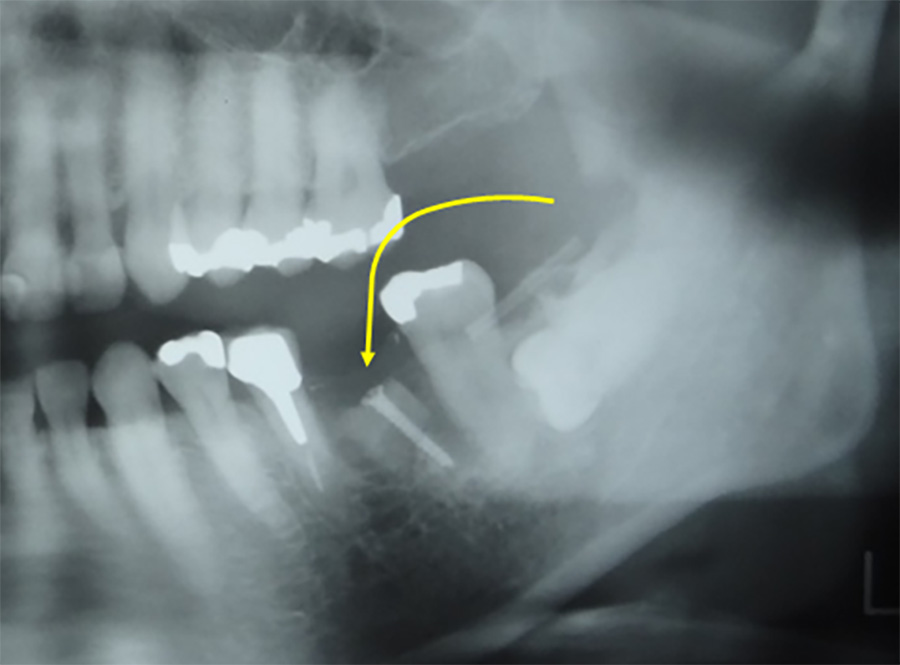

インプラント埋入のために、上顎の奥歯の骨の厚みが足りない場合に骨を作る処置です。もともとの骨の厚みにより、ソケットリフトもしくはサイナスリフトを選択します。骨を作る程度により治療内容や期間はさまざまです。

上顎の骨を持ち上げて同時にインプラントを埋入しました。